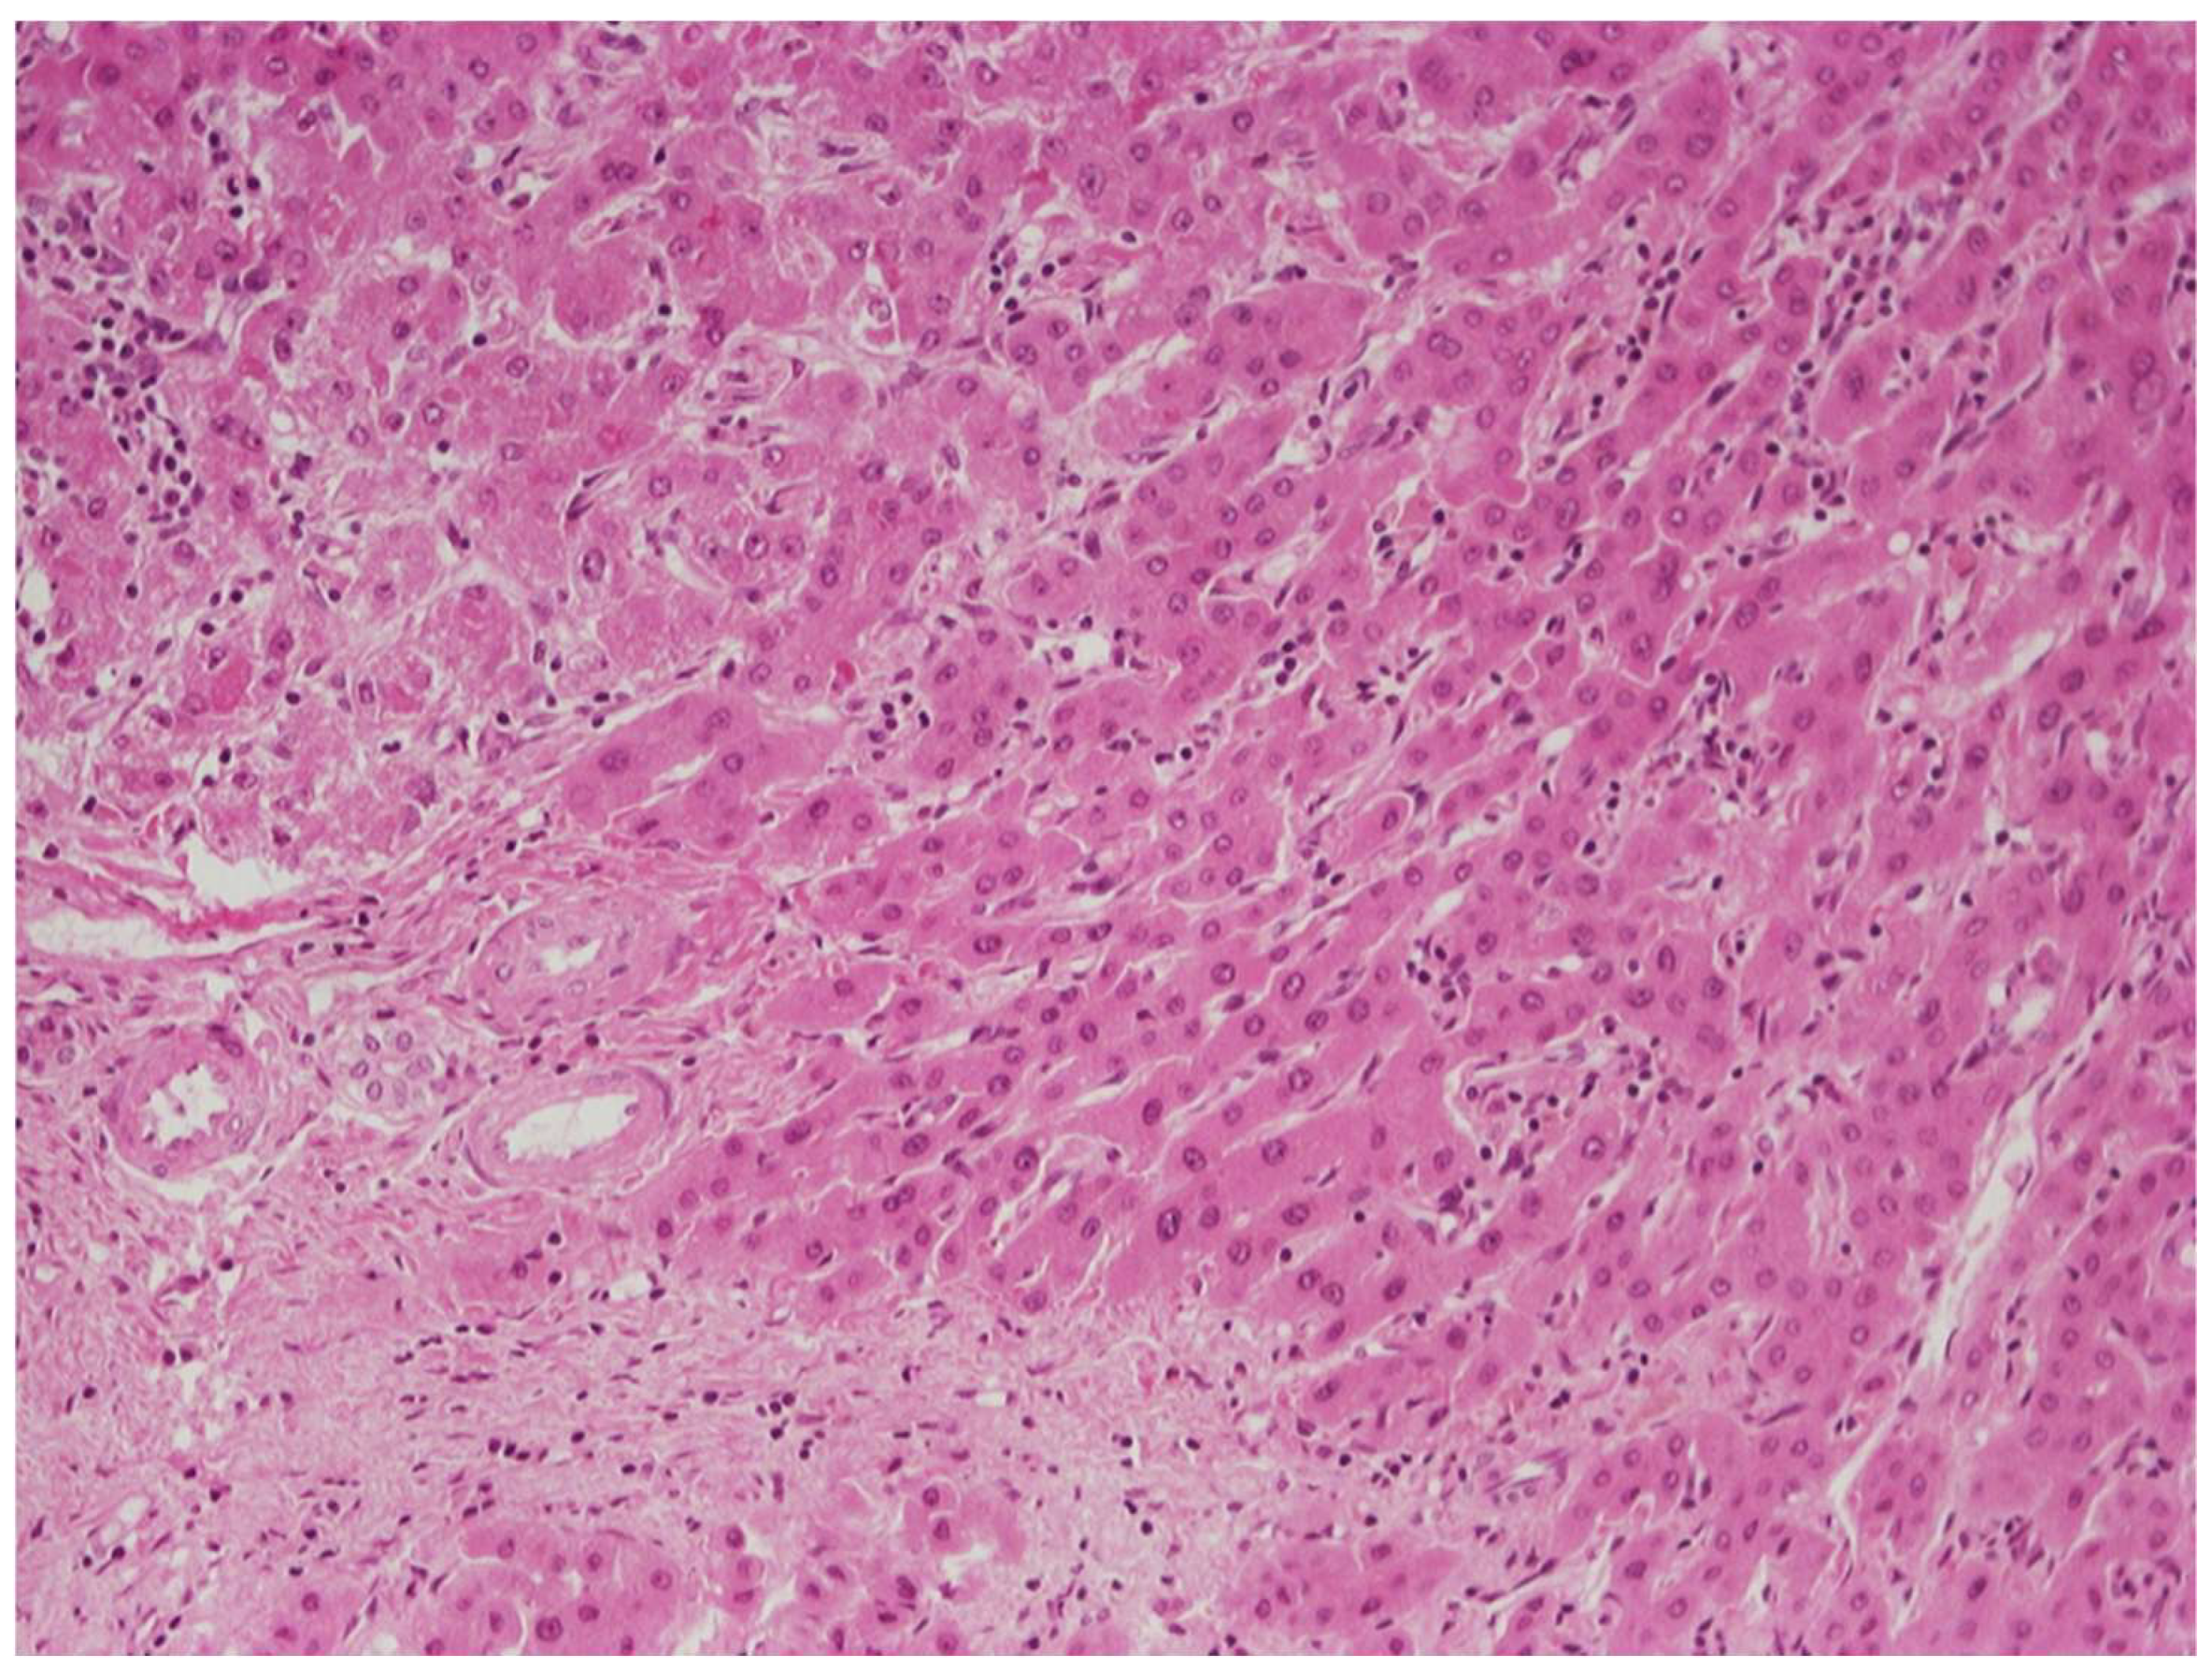

6.1. Low-Grade vs. High-Grade Dysplastic Nodules

6.2. Low-Grade Dysplastic Nodules vs. Large Regenerative Nodules

6.3. High-Grade Dysplastic Nodules vs. Hepatocellular Carcinoma